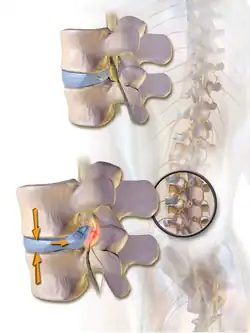

When a tear in the outer, fibrous ring of an intervertebral disc allows the soft, central portion to bulge out beyond the damaged outer rings, the disc is said to be herniated.

When the spine is straight, such as in standing or lying down, internal pressure is equalized on all parts of the discs. While sitting or bending to lift, internal pressure on a disc can move from 1.2 bar (17 psi) (lying down) to over 21 bar (300 psi) (lifting with a rounded back). Herniation of the contents of the disc into the spinal canal often occurs when the anterior side (stomach side) of the disc is compressed while sitting or bending forward, and the contents (nucleus pulposus) get pressed against the tightly stretched and thinned membrane (annulus fibrosus) on the posterior side (back side) of the disc. The combination of membrane-thinning from stretching and increased internal pressure (14 to 21 bar (200 to 300 psi)) can result in the rupture of the confining membrane. The jelly-like contents of the disc then move into the spinal canal, pressing against the spinal nerves, which may produce intense and potentially disabling pain and other symptoms.

Illustration depicting herniated disc and spinal nerve compression